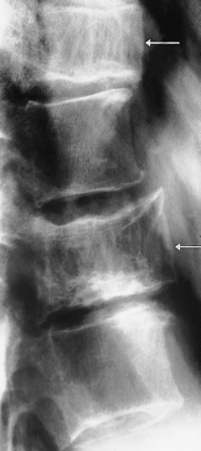

1- Metastases:

particularly from primary tumours of the prostate or breast . Dense vertebra (arrow) due to metastases from carcinoma of the breast.